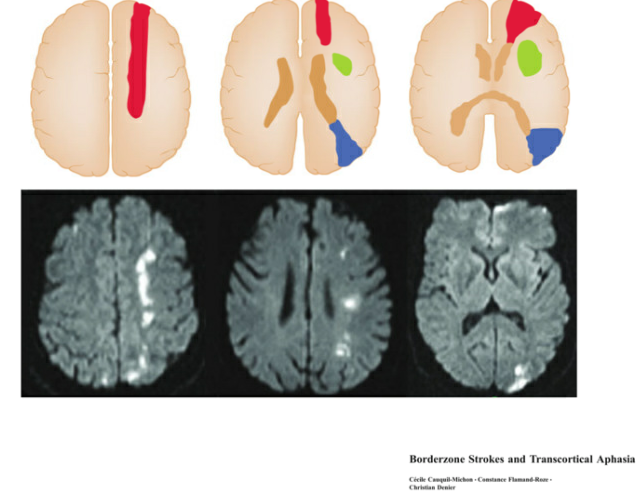

This is a 60-year-old woman with a history of ischemic stroke 5 years ago, previously presenting with aphasia and right-sided weakness, with complete recovery. She now presents with recurrent aphasia and right-sided weakness. In the ED, she was found to have a urinary tract infection with sepsis. MRI brain DWI showed no new diffusion restriction. After 2 days of antibiotics, her neurological deficits completely resolved. Question: What do you see on the MRI? How do you explain her recurrent aphasia and right-sided deficits despite no new imaging changes? #Neuroradiology #Neurology #Stroke #UTI #FOAMed

Patients with intracranial athero should now be targeted to LDL<55 mg/dl, given the new ACC/AHA lipid guidelines. This should be adopted in CAPTIVA and other ongoing trials, as well as routine practice @BrianHoh1 @ESOstroke @WorldStrokeOrg @AHAScience